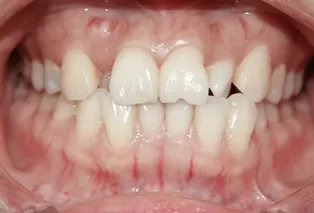

Intraoral photos